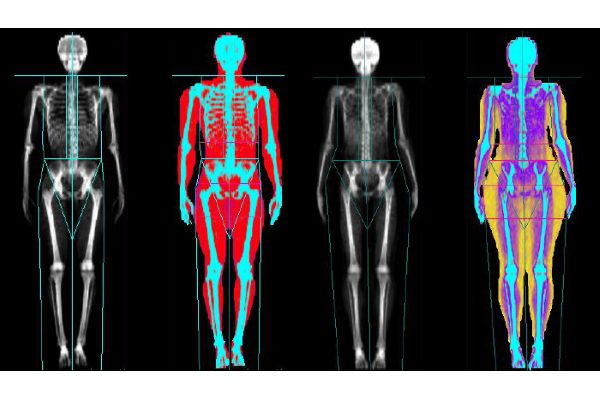

DEXA یا اسکن تراکم استخوان، یک روش پیشرفته برای اندازهگیری تراکم معدنی استخوان است. این فرایند به پزشکان کمک میکند تا سلامت استخوانها را ارزیابی کرده و خطر ابتلا به پوکی استخوان را بررسی کنند. در ادامه، به بررسی روش DEXA و اهمیت آن میپردازیم.

روش DEXA، که مخفف Dual-Energy X-ray Absorptiometry است، یکی از معتبرترین و دقیقترین روشهای سنجش تراکم استخوان به شمار میآید. هدف اصلی این روش، تعیین میزان کلسیم و دیگر مواد معدنی در بافت استخوانی است که به ما کمک میکند تا وضعیت سلامتی استخوانها را ارزیابی کنیم. این روش به ویژه در تشخیص و پیگیری بیماریهایی مانند پوکی استخوان کاربرد دارد. همچنین، DEXA میتواند به پزشکان کمک کند تا خطر شکستگیهای استخوانی را در بیمارانی که در معرض ریسک هستند، ارزیابی کنند. یکی از دیگر روش های آنالیز بدن ، آنالیز با دستگاه آنالیز بدن آنیا است که به آن bia هم میگویند .

یکی دیگر از کاربردهای مهم DEXA، ارزیابی ترکیب بدنی است. این اسکن به پزشکان کمک میکند تا نسبت چربی به توده عضلانی و حجم استخوانی را در افراد اندازهگیری کنند. این اطلاعات به عنوان معیاری برای سنجش سلامت عمومی و همچنین در طراحی برنامههای ورزشی و غذایی برای افراد محسوب میشود. بهویژه در ورزشکاران و افرادی که تحت رژیمهای خاص غذایی هستند، ارزیابی دقیق ترکیب بدنی میتواند به بهبود عملکرد و پیشگیری از آسیبهای ورزشی کمک کند.